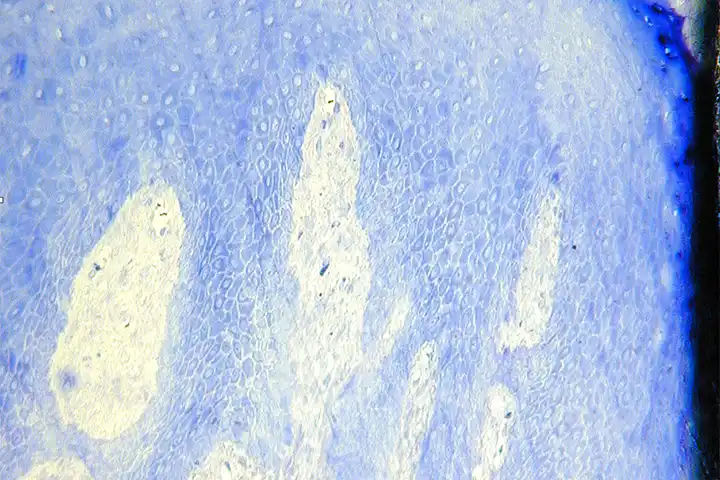

Implant Macro/Micro Design and Surface Engineering

Development and clinical evaluation of:

- Implant macro-geometry and thread design

- Nanotechnologies applied to implant surfaces

- Osteoconductive and osteoinductive surface treatments

- High-stability implant-abutment connections.

Focus: enhanced osseointegration and improved management of compromised sites.